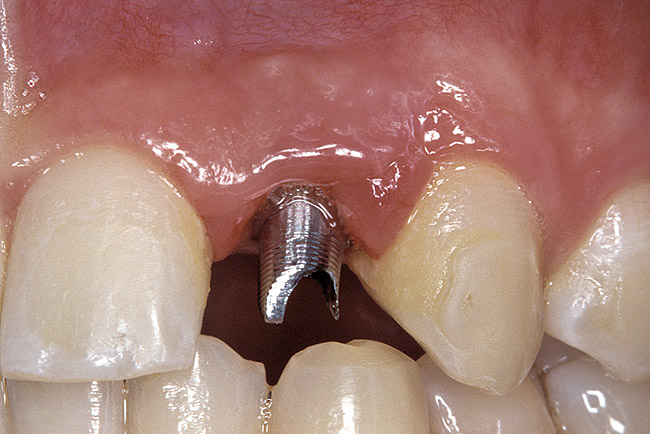

The transitional titanium abutments were left in place for 8 weeks. During this time, the morphologically shaped, computer-milled abutments supported the interproximal tissue and developed the desired emergence profiles. The computer-milled abutments were created to accommodate the adjacent teeth and opposing occlusion, and to aid in the fabrication of the final porcelain-fused-to-metal (PFM) restorations (Figure 41 and Figure 42). The final crowns were delivered 4 months after implant placement. The radiograph of the emergence profile confirmed the seamless fit of the abutment-implant-crown interfaces (Figure 43). The final restorations were esthetic, functional, and met the needs of the patient (Figure 44). The re-establishment of the interdental papilla completed the careful transformation of the flat alveolar crestal tissue into a proper emergence of the clinical PFM crowns, indistinguishable from the surrounding dentition (Figure 45).

Figure 41  IMPLANT PLACEMENT The patient-specific, computer-milled abutments were placed.

Figure 41

Figure 42  IMPLANT PLACEMENT The patient-specific, computer-milled abutments were placed.

Figure 42